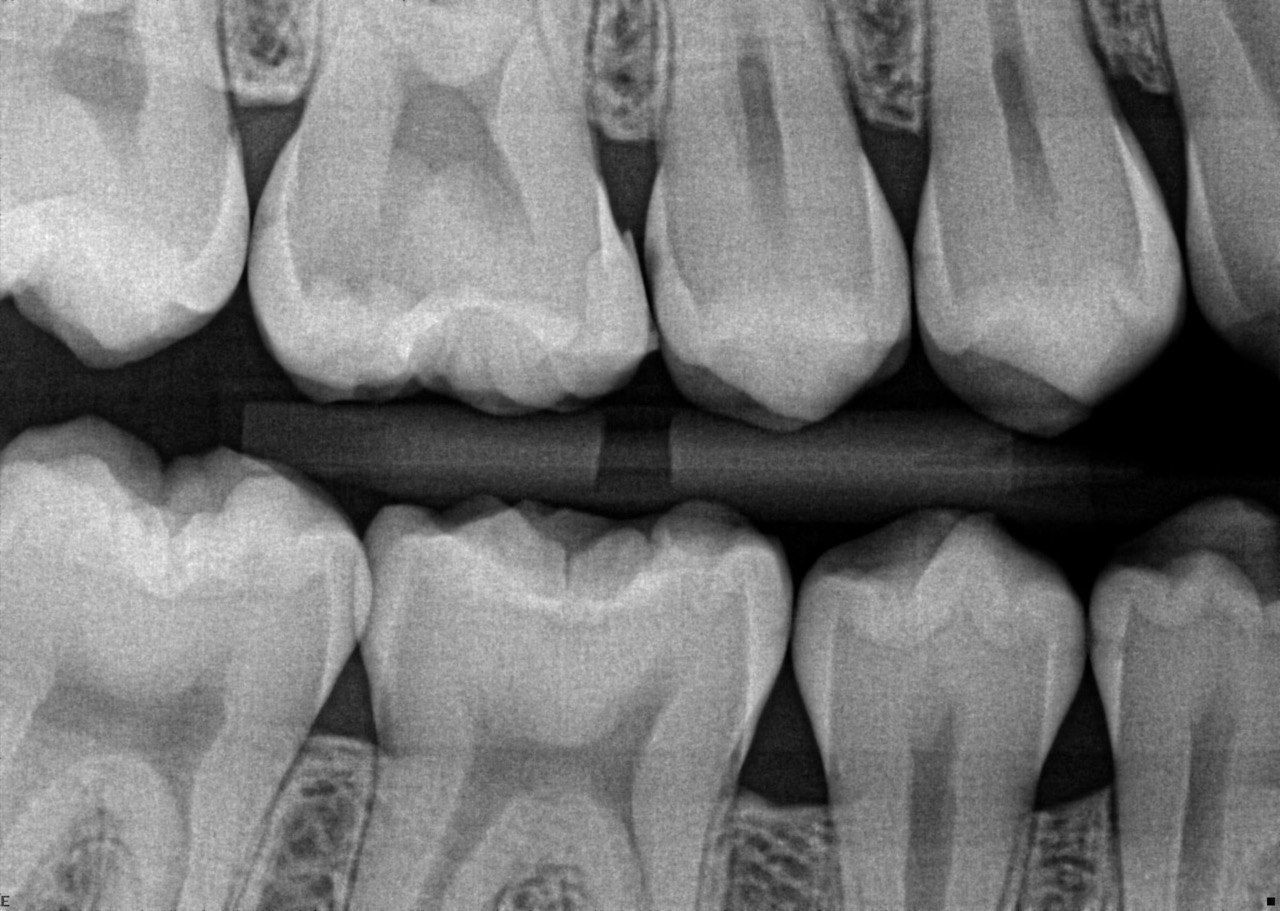

24 / 50

24. What are the caries level in distal surface th # 4.4, Mesial surface tooth # 4.5 respectively?

25 / 50

25. What are the caries level in distal surface of the tooth # 1.4, Mesial surface of the tooth # 1.5 respectively?